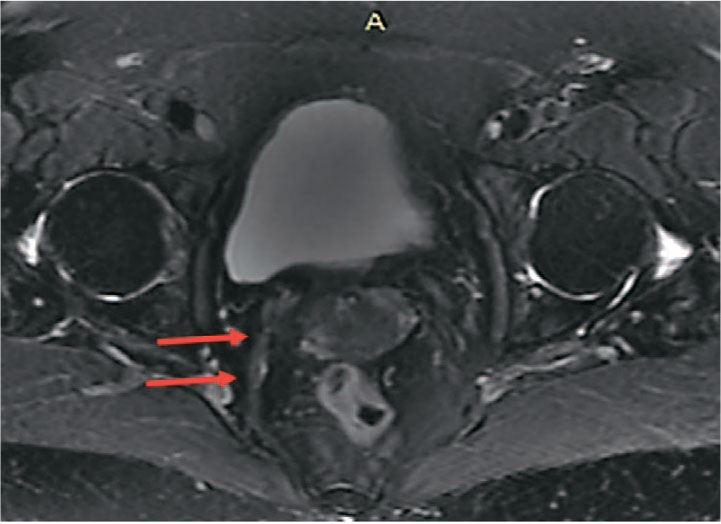

При выполнении МРТ органов малого таза с внутривенным контрастированием препаратом гадолиния спустя более 180 дней после оперативного вмешательства нити импланта с сформированным рубцом дифференцируется как тяж диаметром до 3-5 мм, следующий от сакроспинальной связки до шейки матки, без признаков отека на Т2-ВИ с подавлением сигнала от жира, с отчетливым равномерным накоплением контрастного препарата в позднюю венозную фазу, что характерно для рубцовой ткани (рис. 3-5).

Рис. 5. Пациентка Г. 72 года. МРТ органов малого таза. Т2-ВИ с подавлением сигнала от жира. Имплант с формированной капсулой прослеживается отчетливо, без признаков отека, с изоинтенсивным сигналом (стрелки)

Fig. 5. Patient G, 72 years old. MRI of the pelvic organs. T2-VI with fat signal suppression. The implant with the formed capsule is clearly traceable, without signs of edema, with isointense signal (arrows)

Дополнительные данные, полученные при МРТ органов малого таза с контрастированием, подтвердили отсутствие признаков выраженной воспалительной реакции или хронического отека в зоне имплантации, что свидетельствует о хорошей биосовместимости частично резорбируемого материала, что также ранее было продемонстрировано в экспериментальном исследовании. Визуализация импланта позволила зафиксировать его интеграцию в ткани тазового дна и замещение резорбируемого компонента соединительнотканными структурами. Данный факт позволяет утверждать, что количество нерезорбируемого компонента достаточно для поддержания сформированной соединительнотканной неосвязки.